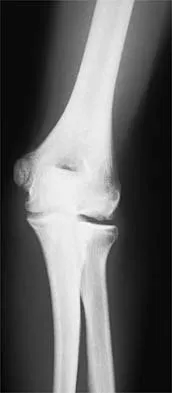

Figures 12a through 12e show the radiograph, MRI scans, and biopsy specimens of a 17-year-old boy. What is the most likely diagnosis?

The images show an epiphyseal lesion. The MRI scan shows extensive bone edema surrounding the lesion, consistent with chondroblastoma. Histology shows polygonal chondroblasts in a cobblestone-like pattern and areas of calcification consistent with chondroblastoma. Although some giant cells are seen, the age of the patient and the polygonal chondroblasts differentiate this lesion from giant cell tumor. Clear cell chondrosarcoma is an epiphyseal lesion that occurs in an older population, and the cells have clear cytoplasm. This lesion is not producing bone on imaging or histologic specimen, eliminating osteosarcoma. Tuberculous septic arthritis can be an epiphyseal lesion, but granulomas would be seen on histology. Menendez LR (ed): Orthopaedic Knowledge Update: Musculoskeletal Tumors. Rosemont, IL, American Academy of Orthopaedic Surgeons, 2002, pp 103-111.